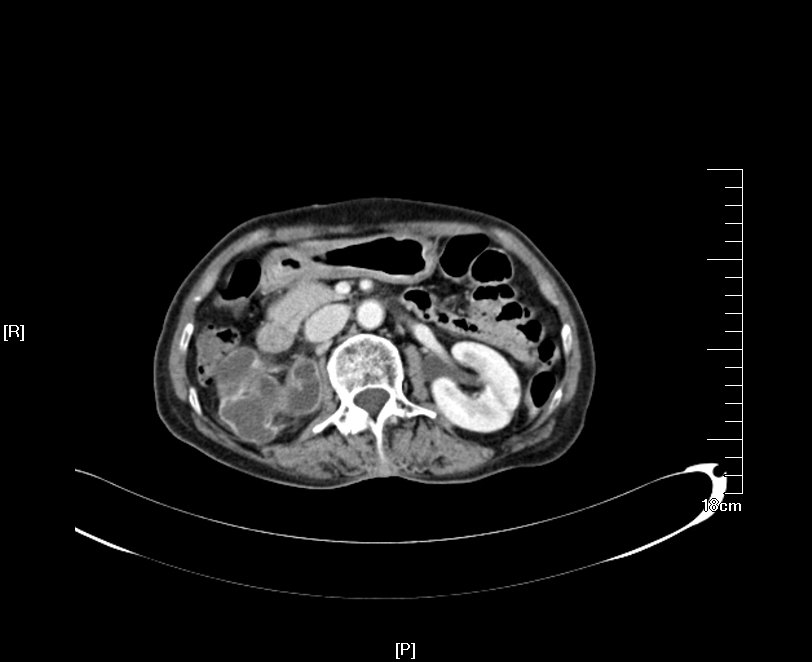

2016年02月手术患者,男性,47岁,河北人,农民,主诉双侧腰部酸胀一年余,伴尿少三天;五年前曾因输尿管结石在当地予以震波碎石3次,后疼痛缓解后未重视,五年来未予以复查,三天前出现尿少,腰部酸胀加重与当地医院就诊后发现病情危重遂来我院求诊,CT:双侧肾脏重度积水,皮质菲薄,双侧输尿管上段扩张明显,双侧输尿管中段结石,左侧结石约1.7cm,右侧约2.8cm左右,GFR:左侧11.7ml/min,右侧16.1ml/min。肾功能:Cr 516umol/L;术前诊断:双侧输尿管结石 双肾重度积水 肾功能失代偿;行双侧经皮肾穿刺造瘘术,保护肾功能,十天后Cr下降至236umol/L,方行双侧输尿管镜检,但由于输尿管梗阻时间太长,输尿管迂曲扩张明显,中段输尿管与周围脏器严重黏连,输尿管镜无法顺利上行,遂行双侧输尿管切开取石术+双侧输尿管裁剪成型术。

CT检查提示:双侧肾脏重度积水双侧输尿管中段结石 双侧输尿管上段积水扩张